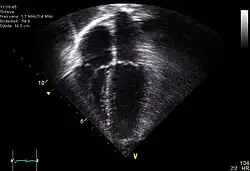

Le cœur est un organe intra thoracique, entouré d'air (les poumons) et d'os (les côtes). Ces deux dernières structures ne laissent pas transmettre les ultrasons, rendant l'examen plus complexe. On se sert ainsi d'un nombre limité de « fenêtres » anatomiques, lieux où le cœur peut être visualisé par l'échocardiographie, sans interposition aérienne ou osseuse.

Le cœur est un organe tridimensionnel mobile. La prise en compte de cette quatrième dimension (le temps) est nécessaire pour une bonne appréhension de l'organe dans sa globalité. Cela nécessite une résolution temporelle suffisante pouvant être caractérisée par la cadence d'acquisition des images : elle doit être au moins d'une vingtaine images/s et idéalement supérieure à 50 images/s (pour permettre une visualisation correcte en ralenti, surtout si la fréquence cardiaque est élevée). De même, l'analyse à l'aide d'une image, par essence, bidimensionnelle, d'un organe quadridimensionnel, impose certains artifices : c'est le mode Tm (pour l' anglais : time motion), utilisé de manière courante, avec en abscisse le déroulement du temps et en ordonnée les échos détectés sur une seule ligne de tir.

- Le cœur est un organe tridimensionnel battant. L'échocardiographie effectue des coupes de cet organe et les résultats peuvent varier suivant le plan de coupe choisi. L'examen reste dépendant de l'expérience de l'examinateur.

Échographie tridimensionnelle